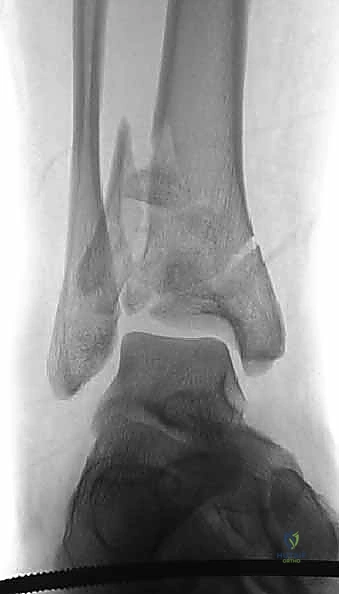

1. التصوير بالأشعة السينية التقليدية (X-Rays)

يتم أخذ صور من ثلاث زوايا (أمامية خلفية AP، جانبية Lateral، ومورتيس Mortise). تعطي هذه الصور فكرة عامة عن نمط الكسر، قصر الساق، ومدى انزياح العظام.

2. التصوير المقطعي المحوسب (CT Scan) - المعيار الذهبي

لا يمكن إجراء جراحة حديثة لكسر البيلون دون إجراء أشعة مقطعية. لماذا؟

كشفت الأبحاث المتقدمة (مثل أبحاث كول Cole وزملائه) والتي يعتمد عليها الدكتور هطيف، أن الأشعة المقطعية، وخاصة مع إعادة البناء ثلاثي الأبعاد (3D Reconstruction)، تسمح برسم خريطة دقيقة لكل قطعة عظمية مفتتة في السطح المفصلي (AO/OTA 43-C3).